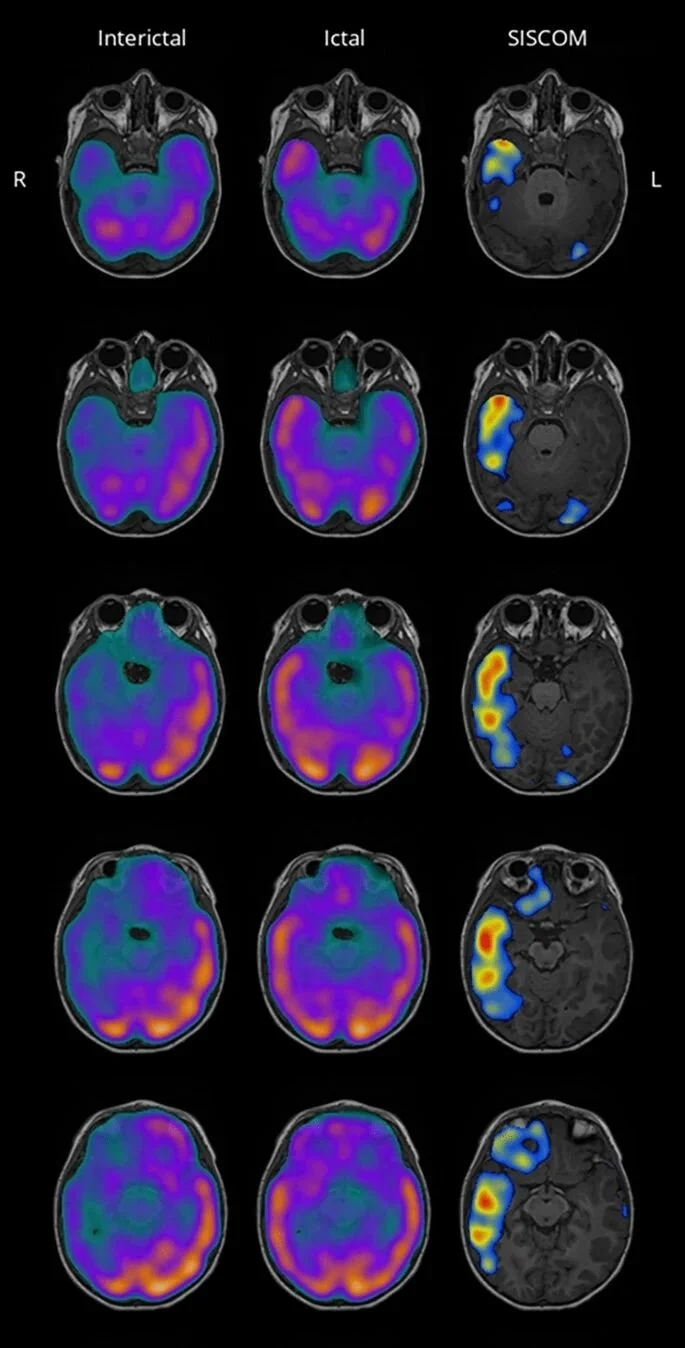

From the paper: “Subtraction ictal single-photon emission computed tomography (SPECT) coregistered to MRI (SISCOM) is a well-established technique for quantitative analysis of ictal vs interictal SPECT images that can contribute to the identification of the seizure onset zone in patients with drug‐resistant epilepsy. However, there is presently a lack of user-friendly free and open-source software to compute SISCOM results from raw SPECT and MRI images. We aimed to develop a simple graphical desktop application for computing SISCOM. MNI SISCOM is a new free and open-source software application for computing SISCOM and producing practical MRI/SPECT/SISCOM image panels for review and reporting. The graphical interface allows any user to quickly and easily obtain SISCOM images with minimal user interaction. Additionally, MNI SISCOM provides command line and Python interfaces for users who would like to integrate these features into their own scripts and pipelines. MNI SISCOM is freely available for download.”